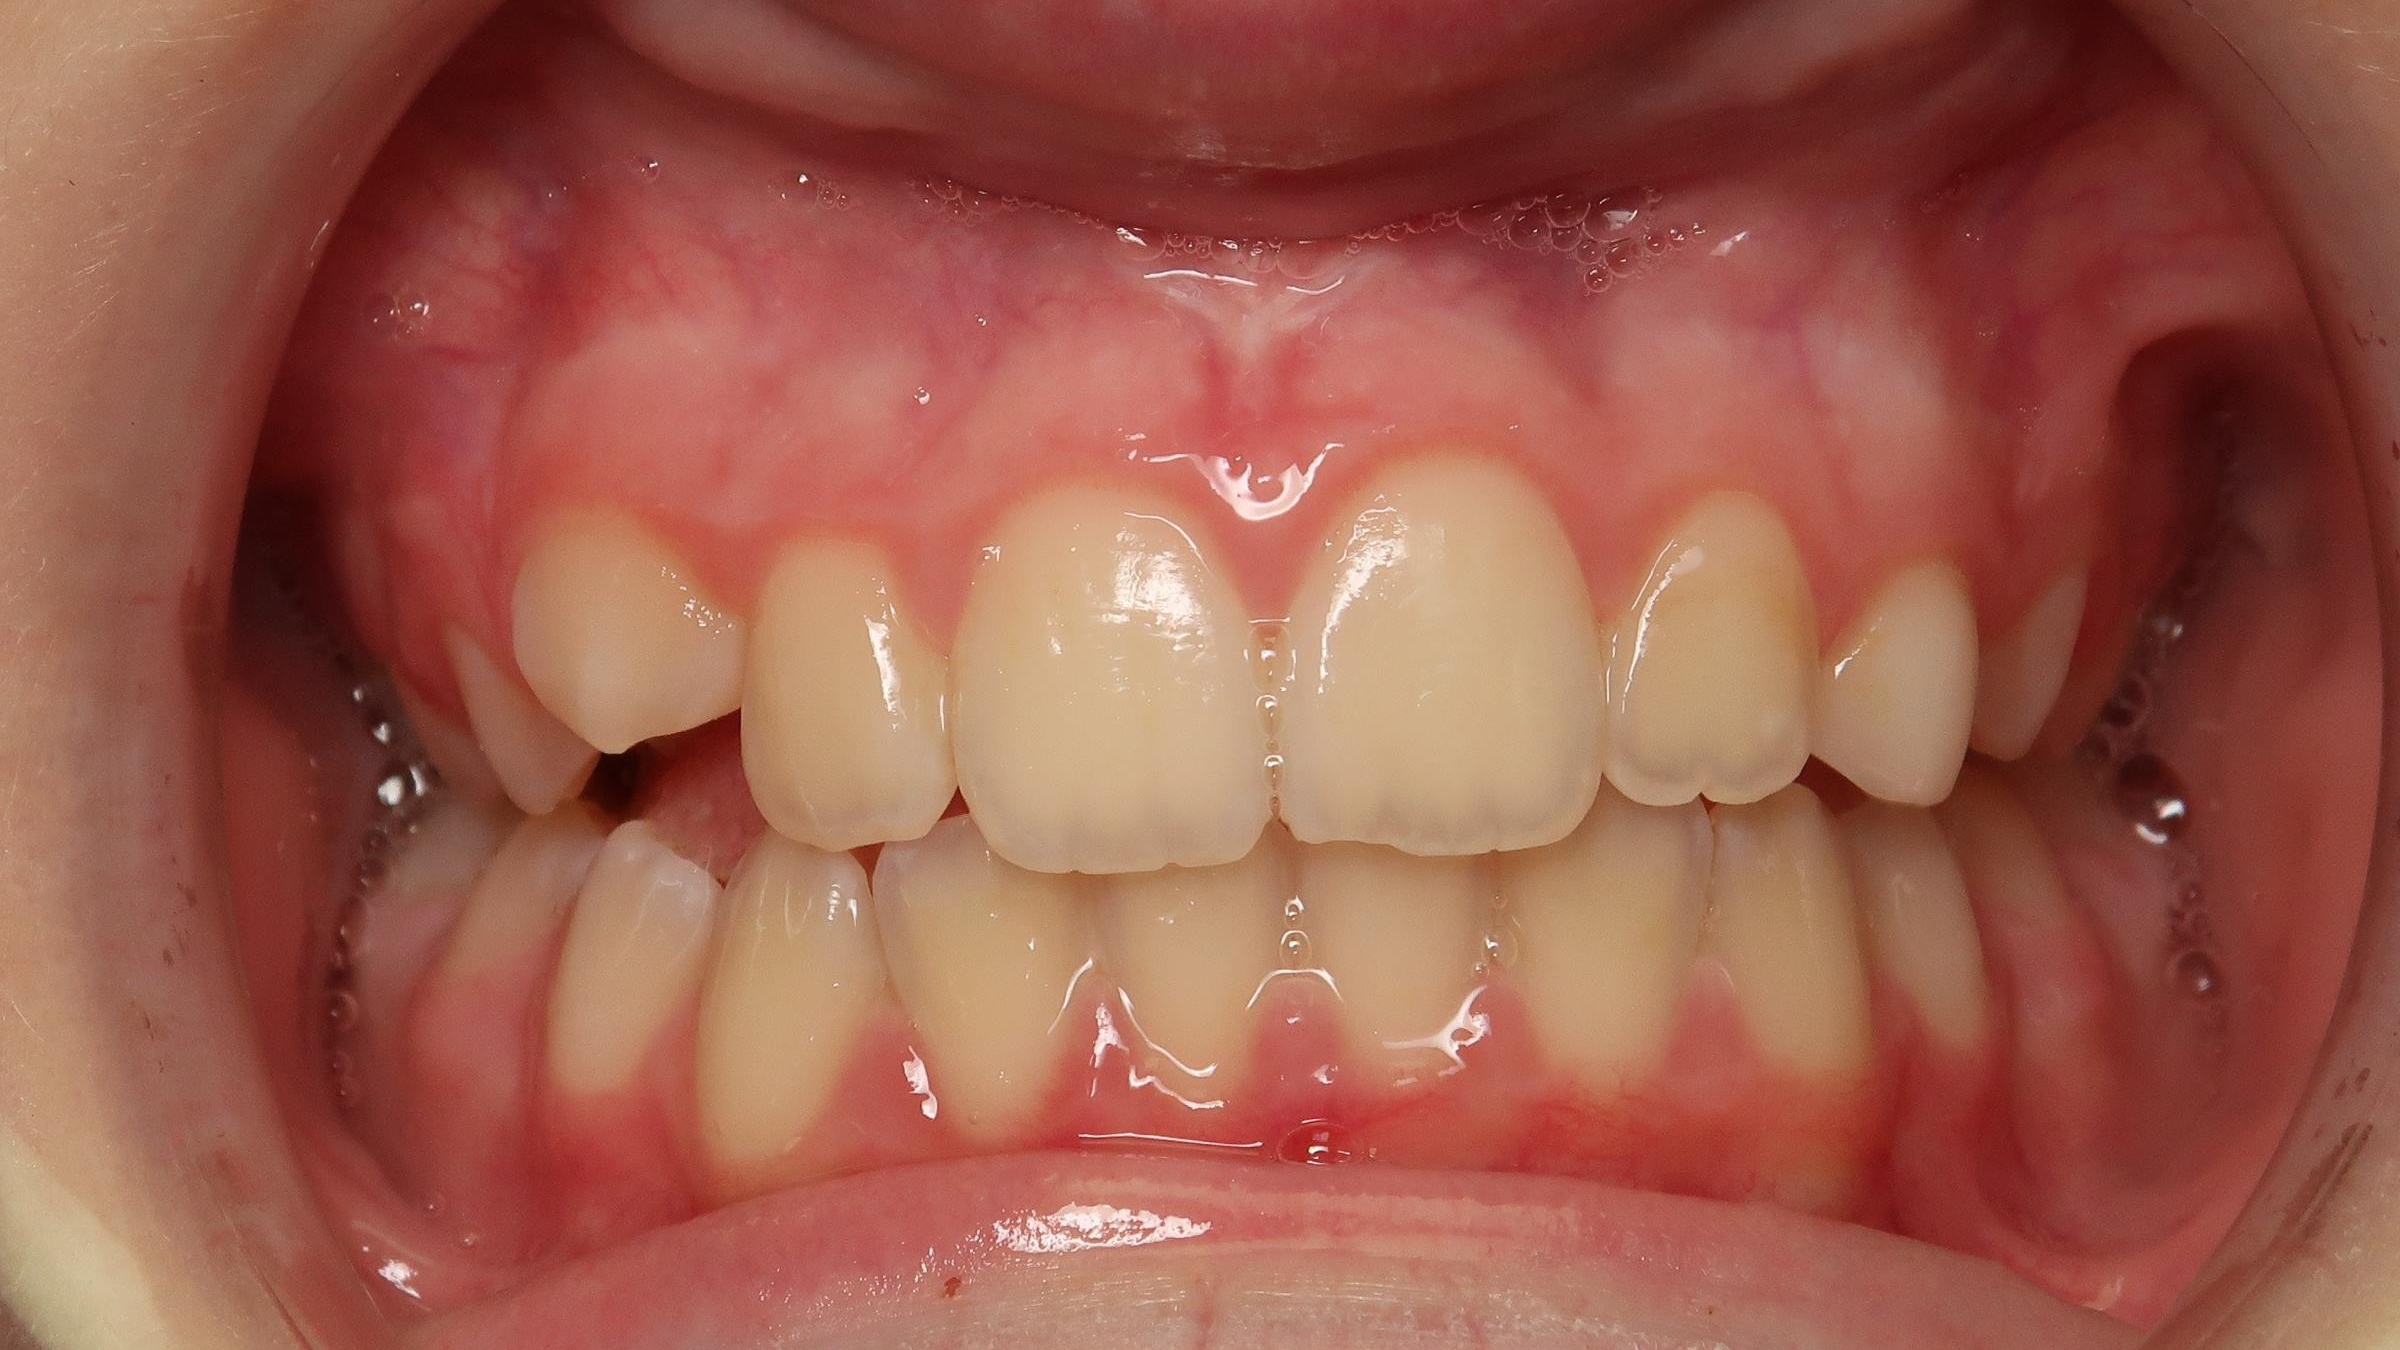

18 béance inversé droit 4 ans

inversion des dents postérieur et espace entre l'arcade du haut et du bas (béance)

bilan de début et en cours de traitement